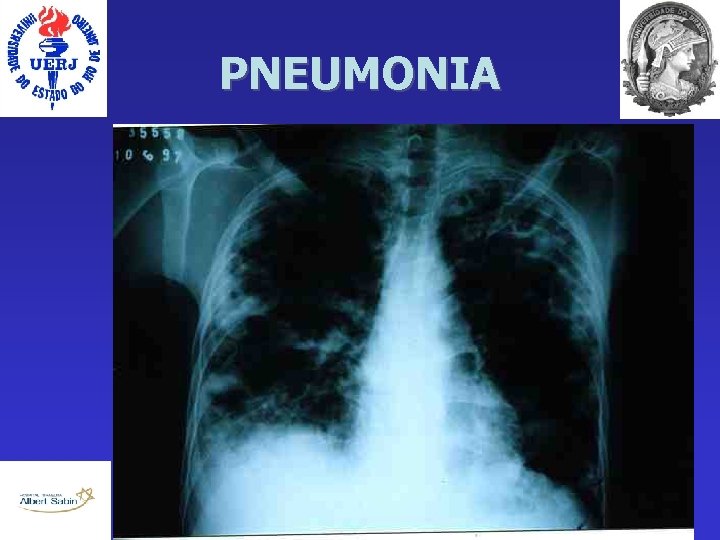

Diagnóstico Clínico 1) Presença de novo infiltrado pulmonar no Rx tórax OU persistência/progressão de infiltrado pulmonar no Rx tórax, por 2 dias consecutivos 2) Febre (>38 o C) OU Leucocitose > 12. 000 OU Bastões > 10% OU Leucopenia < 4. 000 3) Mudança do aspecto da secreção traqueal OU piora da troca gasosa